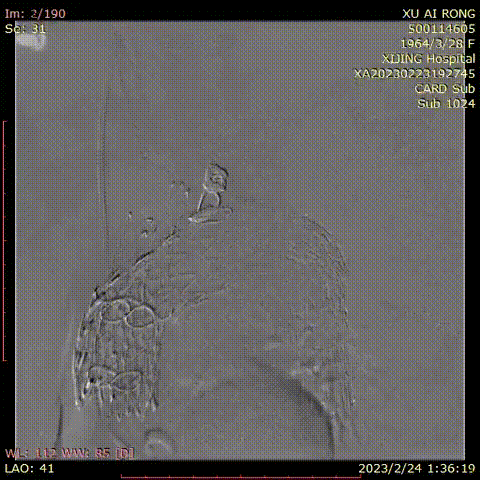

★ 病例4

王某,女,56岁,“突发胸背痛15小时”入院,主动脉CTA提示:升主动脉-腹主动脉管腔外可见新月形低密度影,主动脉弓前部可见溃疡,大小约0.6cm。

术前CTA

术前造影

术后造影

手术用时 95分钟